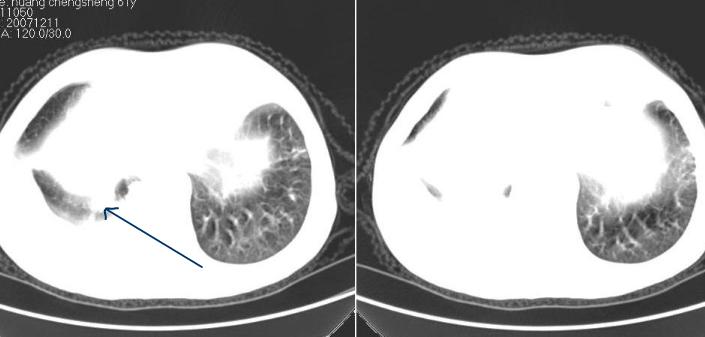

补充一下:右肺底好象有一个类圆形的结节影,可考虑为肺部转移。如图示。[

[本贴已被 徐中佑 于 2007-12-12 19:20:02 修改过]